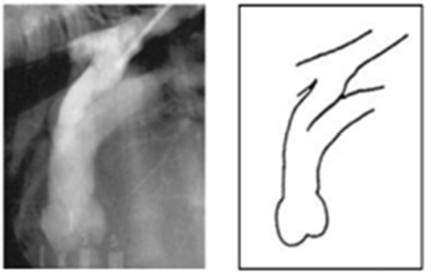

| MVI + CTR (CTR = chordae tendineae rupture), bivalvular |

![]() |

| - Mitral & Tricuspid valve 모두 이상 ⇒ Lt. & Rt. atrium 모두 볼록 - Lt. auricle, LA 확장 ⇒ Trachea elevation, Caudal waist 소실, tall heart ☑️ 흉수(pleural effusion) : 우심부전 시 주로 흉수, 복수 (체순환 혈액 받아들이지X) : 우심 valve 이상 → 폐로 가는 혈액량 감소 → 우심방 비대, 혈액 정체, congestion → 전신 정맥압 상승 → pleural cavity의 모세혈관 압력 증가, 수분 누출 → 흉막강에 체액 축적 ⇒ 심장 주위 뿌옇게 물 참. 흉수 때문에 폐가 팽창하지 못해서(collapsed), 빈호흡, 호흡곤란, 산소 포화도 감소, 청색증 (*Thoracocentesis 필요) ☑️ 폐수종(pulmonary edema), 폐출혈 : 주로 좌심부전과 연관 (폐순환 혈액 받아들이지X) : 폐정맥압, 폐모세혈관압이 상승(pulmonary vein hypertension) → 물이 빠져나와 폐포 공간으로 축적. : pulmonary vein, post capillary hypertension → 압력 너무 높아져서 터지면 폐출혈 ☑️ 호흡을 잘 못해서 위에 공기가 참 (Airophagia) ☑️ Heart failure → cardiac output 감소, hypotension(동맥), 기침, 기절 등 |